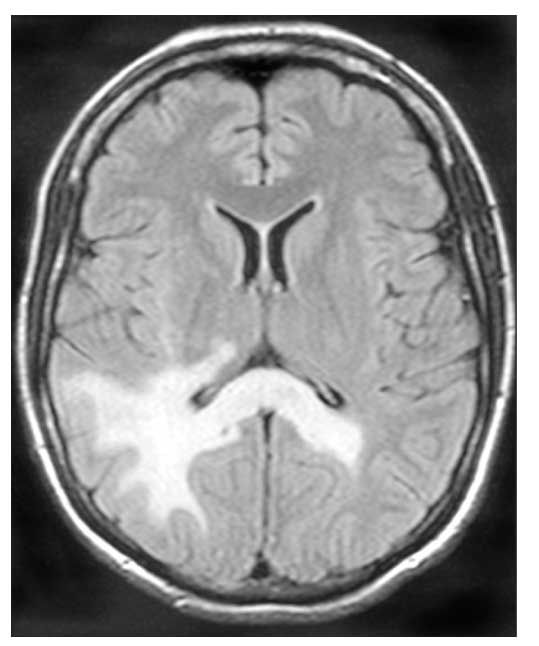

The patient's MRI scans showed abnormal signal in subcortical white matter of the right cerebral occipital/temporal regions on fluid-attenuated inversion recovery (FLAIR)/T2-weighted images (ie, weighting schematic for MRI in which damaged tissues are hyperintense). Although malignancy was considered, the MRI findings were most consistent with progressive multifocal leukoencephalopathy.

Figure 2. Brain MRI scan at presentation displays signal abnormalities on fluid-attenuated inversion recovery/T2-weighted sequence. Lesions involve the temporal/occipital lobes and corpus callosum. Lesions are hyperintense on the T2-weighted image. There was no abnormal enhancement with gadolinium, and no mass effect.

An antiretroviral regimen of tenofovir, emtricitabine, and lopinavir/ritonavir was started. Within 4 weeks, the patient's HIV-1 RNA level declined to less than 75 copies/mL. However, her CD4 count did not improve over a 2-month period. Clinical deterioration was heralded by worsening left-sided weakness and the sudden development of blindness. Serial brain MRI scans obtained over a 45-day period showed extensive progression of the lesions that accompanied the neurological changes (Figures 2 and 3). Immune reconstitution inflammatory syndrome (IRIS) was considered, although many diagnostic features were not present; however, neurological deterioration prohibited additional brain biopsies. Nevertheless, glucocorticoid treatment was initiated but without success. The patient experienced progressive weakness and died of respiratory failure 3 months after her initial MRI.

Diagnosis of PML is based on clinical findings, neuroradiographic imaging, and virological testing. Fifty-three percent of patients with PML present with hemiparesis, and 43% present with cognitive impairment. Other, less frequent presentations include speech or visual deficits, ataxia, and seizures.4 Classic MRI findings are well-demarcated, asymmetric lesions in periventricular and subcortical white matter. The lesions are characteristically hyperintense on FLAIR/T2-weighted images, hypointense on T1-weighted images, and non-enhancing with gadolinium and do not create mass effect.4 JCV DNA can often be isolated from CSF by PCR. However, early use of antiretroviral therapy may allow rapid CSF clearance, and the sensitivity of CSF PCR in some studies is estimated to be as low as 53%.3 Brain biopsy is the gold standard for diagnosis of PML, with tissue samples showing JCV infection of oligodendrocytes, associated demyelination, and reactive changes.3